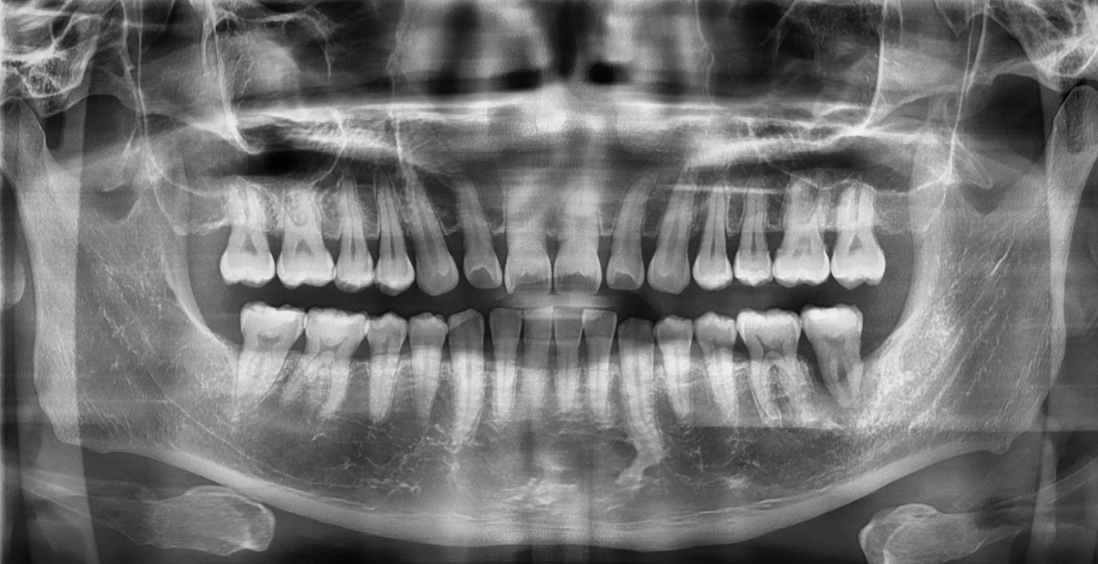

CASE 2 : 상악동 거상술 (치료기간 : 3개월)

*치료과정에서 부작용이 발생할 수 있으므로

정확한 진단과 수술이 요구됩니다.

BEFORE

AFTER